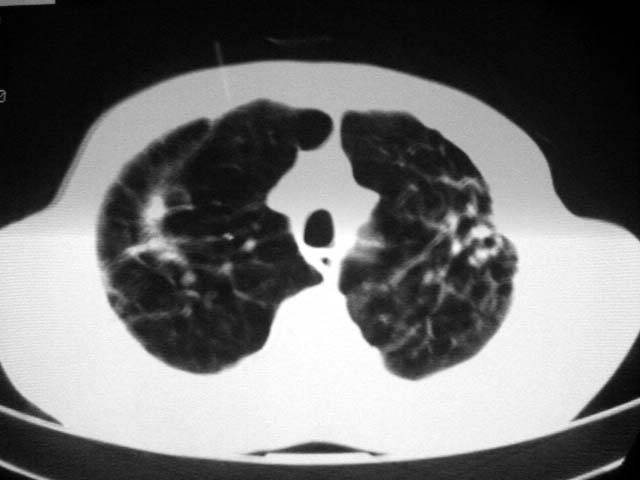

以下是引用zjzjr在2007-9-4 17:00:00的发言:[br]双上肺继发型结核伴左上肺空洞形成.慢性支气管炎伴肺气肿.

以下是引用liuzheng_9326在2007-9-4 16:23:00的发言:[br]痰检未见结核菌, 治疗后症状好转。图像符合陈旧性结核伴感染。